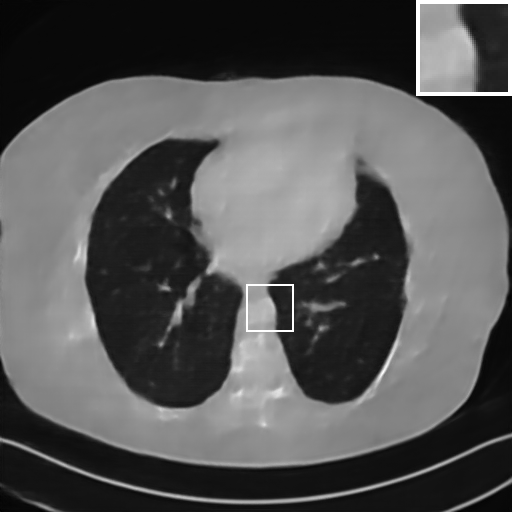

Fig. 4 presents the reconstruction results and residual images obtained by different methods for limited-angle reconstruction. As can be seen, the learning-based methods outperform the direct method and TV model, which exhibit serious artifacts in the missing angle region. Although the denoiser introduced by the FBP-Unet can somehow deal with the noises, the result still presents obvious artifacts. Compared to the SIPID, PD-net and FSR-nets, our LRIP-net1/2 can better preserve the image details and edges with less information left in the residual images. Thus, both the quantitative and qualitative results confirm that the low-to-high double-resolution strategy can improve the reconstruction accuracy for the limited-angle reconstruction problem.

We observe that the low-resolution image prior plays an important role in our method. More specifically, we compare the results of our LRIP-net with respect to different low-resolution priors, which are obtained by down-sampling rate of 1/2, 1/4, and 1/8, respectively. As can be seen in Table III, the best reconstruction results are obtained with the image prior reconstructed by the down-sampling rate of for 150∘, 120∘ and 90∘ limited-angle reconstruction. The visual comparison based on different image priors are also provided in Fig. 5, where obviously less artifacts are left in the reconstruction image by LRIP-net1/8. By comparing the running time, it is easy to see that the smaller the low-resolution image prior, the faster the LRIP-net works.

We further increase the noise level contained in the raw data to 10% white Gaussian noises and list the quantitative results in Table IV. It can be observed that the reconstruction performance of the TV model is poor in the case of high-level noises with PSNR dropping by 4 to 5 dB compared to the previous experiments. On the other hand, the performance of the learning-based methods is less sensitive to noises. The SIPID method relying on the sinogram interpolation works better than FBP-Unet. And the deep unrolling methods (i.e., PD-net, IFSR-net, SFSR-net) outperform the traditional iterative algorithm when the scanning range is limited and data is corrupted by noises. Similar to the previous experiments, compared with other deep learning algorithms, our LRIP-nets give the reconstruction results with higher PSNR and SSIM. Moreover, the low-resolution image obtained by the projection data down-sampled with rate 1/8 always gives the best reconstruction results with more than 2 dB PSNR and 0.05 SSIM increments compared to the PD-net. Fig. 6 illustrates the reconstructed images from different methodologies with scanning angular range of and 10% Gaussian noises. It can be seen that the both TV model and the FBP-Unet suffers from significant artifacts, which present distortions in the angular range of the missing scan. Other learning-based methods provides better visual qualities than FBP-Unet, and our LRIP-net1/8 still gives the best reconstruction result with correct boundaries and fine structures.